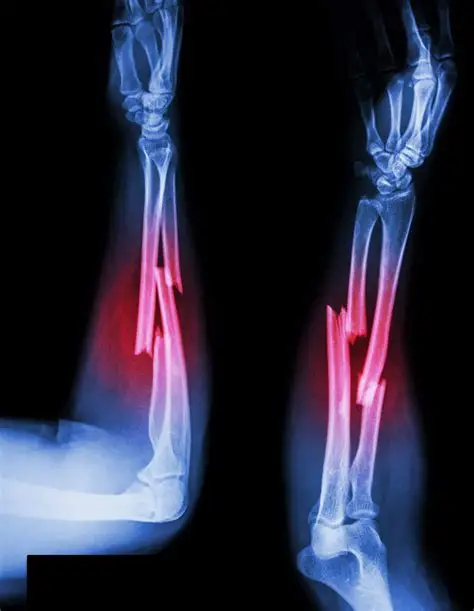

Forearm Fractures

Galeazzi Fracture